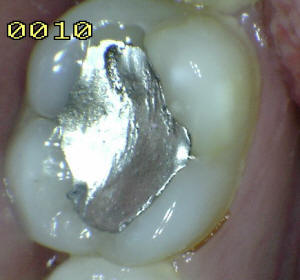

Sistema Internacional para la Detección y Evaluación de Caries (ICDAS)

¿Determine los códigos pertinentes a cada imagen?

Click en el hipervínculo: Para comparar el resultado de su diagnóstico